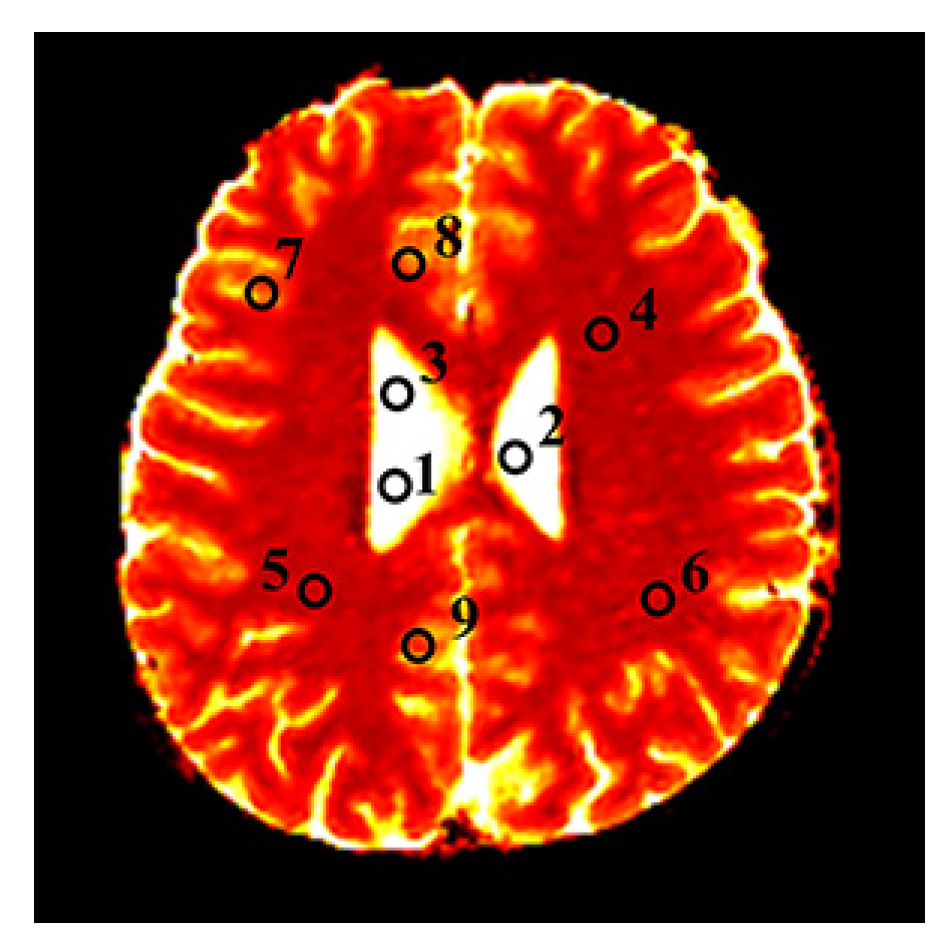

3.3. In Vivo Experimental Results